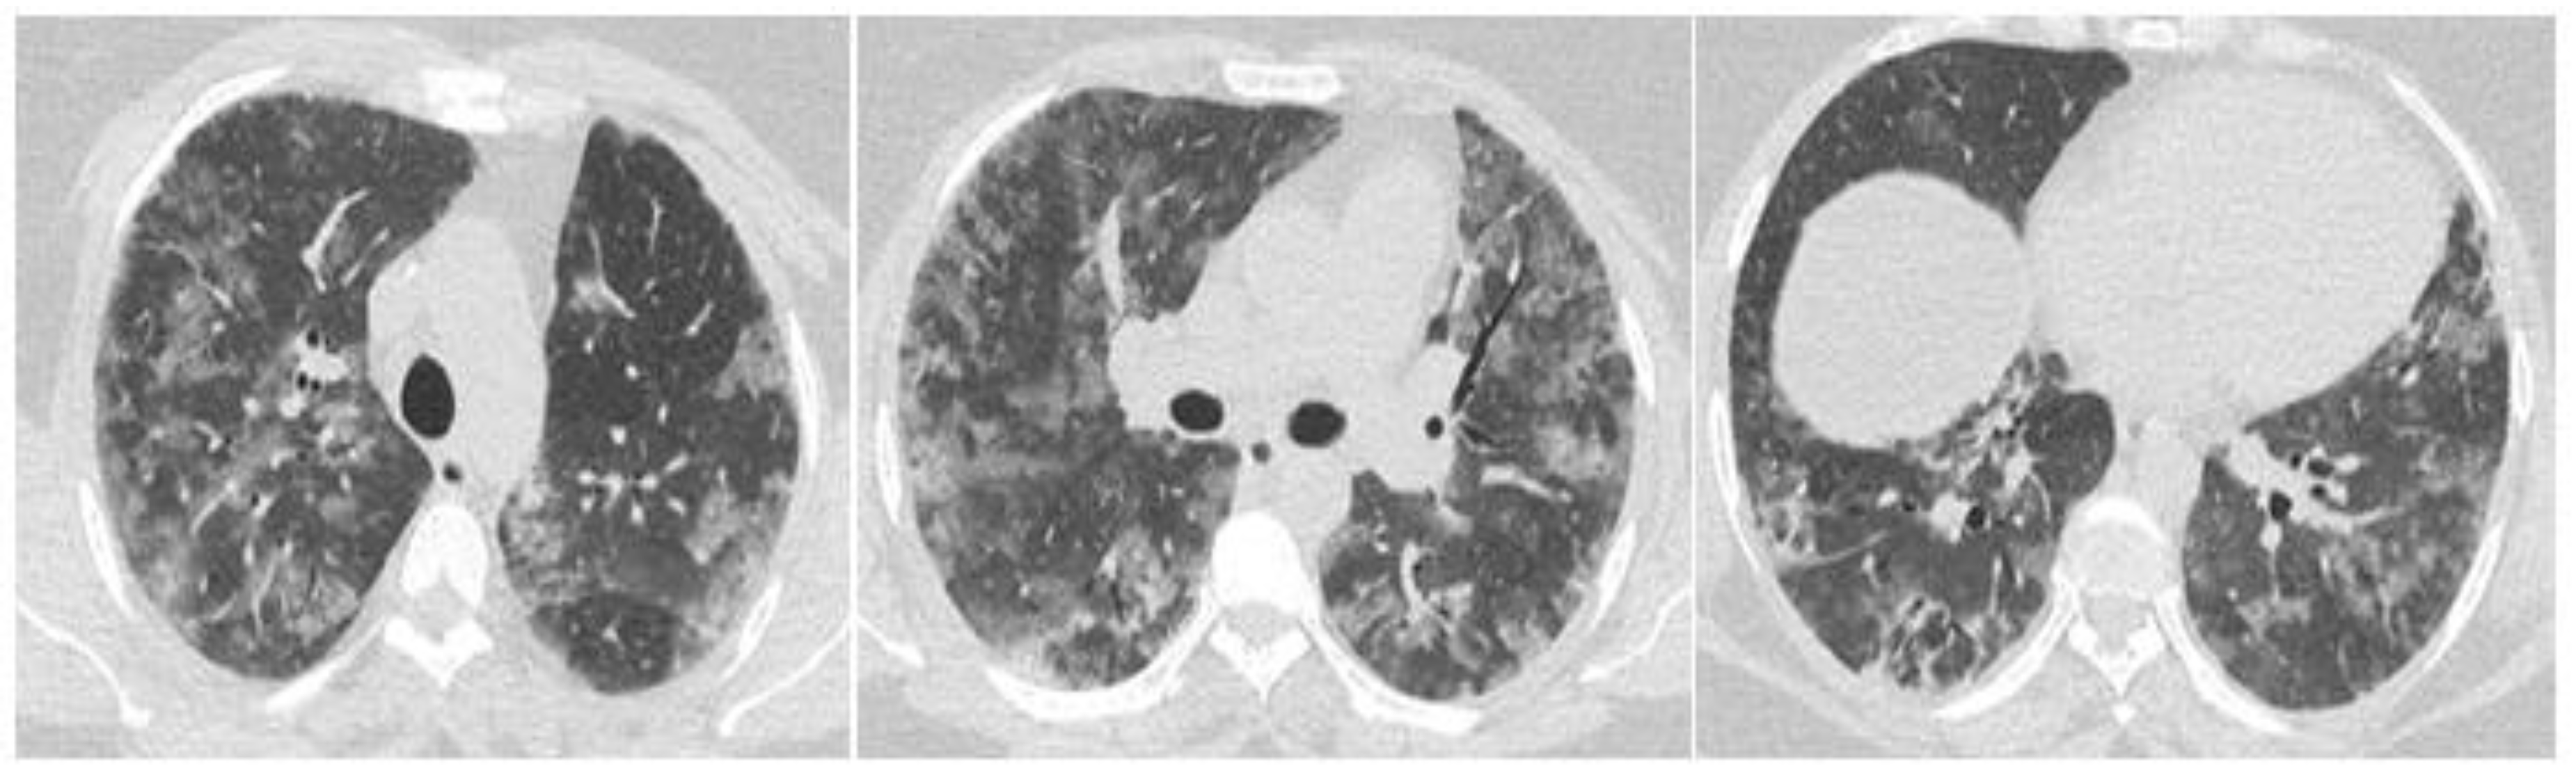

2. Case Report